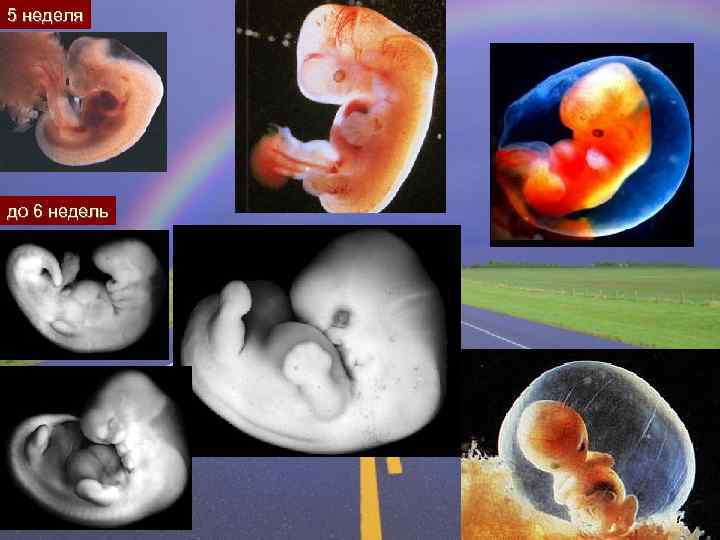

5 неделя до 6 недель

6 недель. 40 дней: можно увидеть плаценту, пуповину и эмбрион Эмбрион 8 мм. На УЗИ определяется сердечная пульсация.